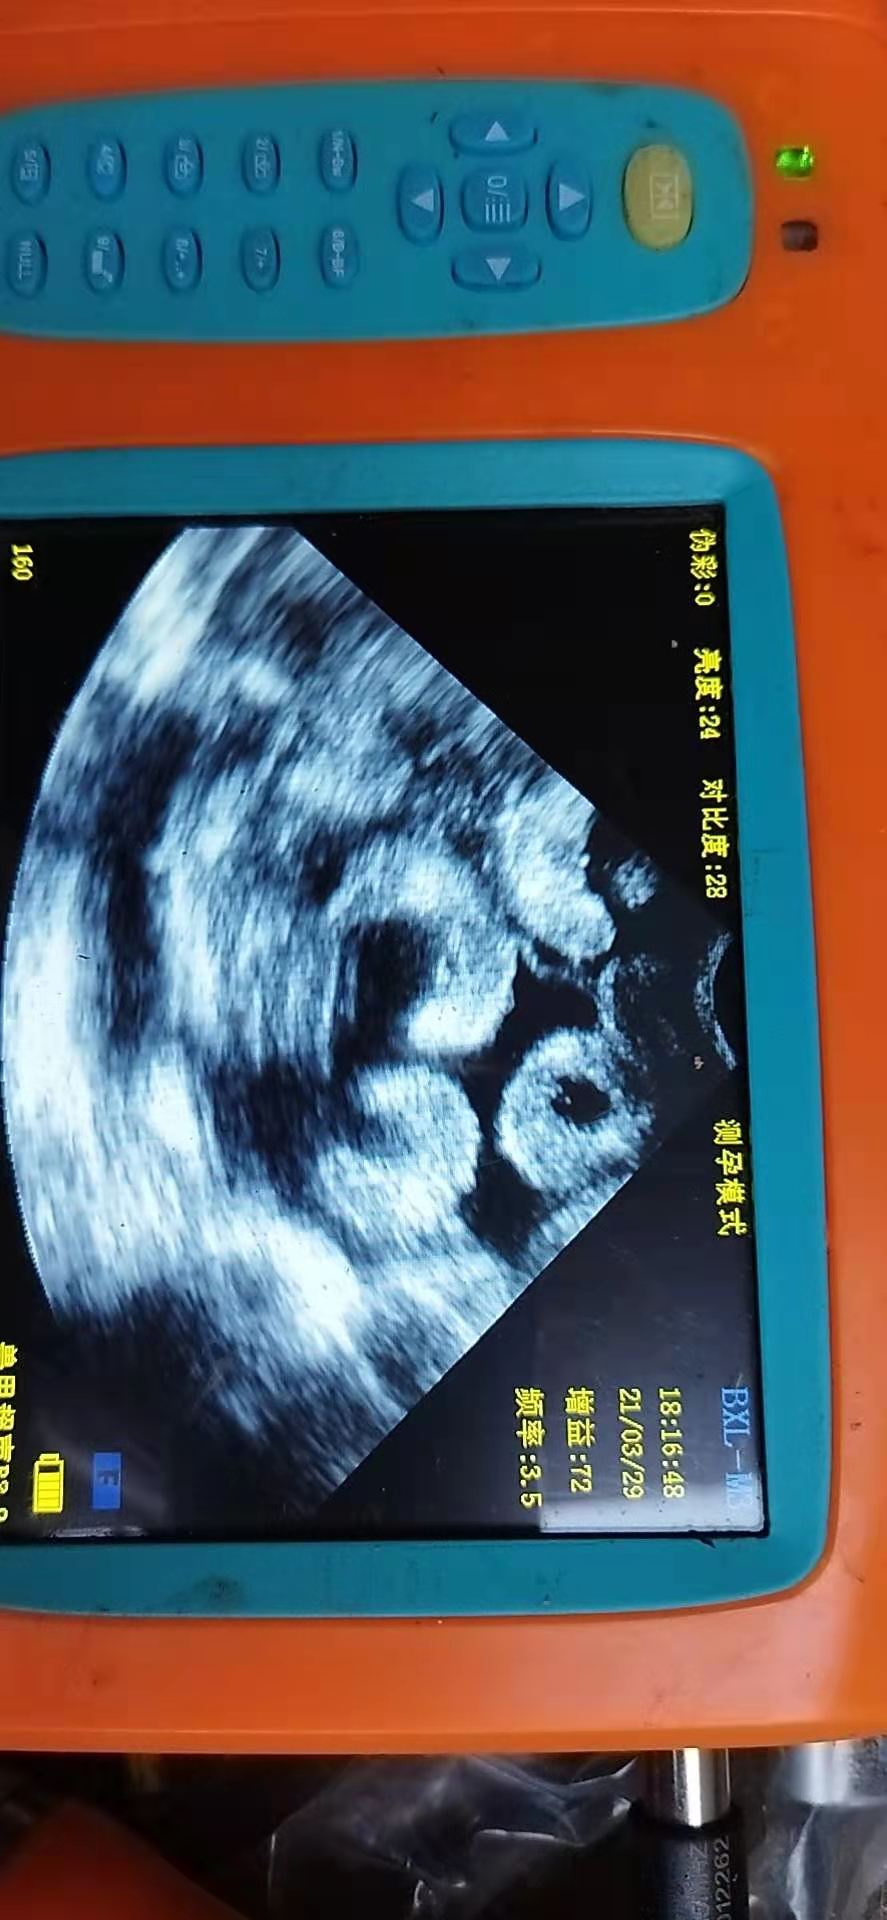

兽用B超仪检测怀孕母羊的超声图像特点

根据怀孕的不同阶段,对怀孕子宫的超声图像的解释可以得出以下两个结论之一:即可能怀孕,但可能需要重新检查或该动物已怀孕。兽医从业者的目的是能够准确得出后一个结论。

可能怀孕的子宫的***个超声检查征兆是子宫中一些充满液体的腔室,兽用B超仪直肠检测可以比比经腹部检测早几天观察到。使用经直肠途径观察到怀孕母羊的子宫积液,有时早在第16天至第20天之间,但有规律地在第20天至第23天之间。从第30天起,在所有情况下都可以看到胎儿。作者的经验是,在第30天对怀孕的山羊进行直肠扫描时,并不总是可以看到胎儿。

在经腹部扫描期间,子宫腔内的液体是从第22天开始观察到的妊娠的***个迹象。尤其是在山羊中,应该认识到可靠的妊娠诊断不能仅仅基于子宫内液体的存在。因此,应基于体液与胎盘和/或胎儿部分或胎膜的存在。从第25天起,有时腹部可以观察到胎儿和胎膜,大多数情况是从30天起,但是在第35天后的所有情况下都应该可见。大约25天时,随着子宫壁的小隆起,可以看到胎盘组发育的***个超声检查迹象。从第38天左右开始,可以观察到胎盘的超声特征:半月形或白色圆形结构(无回声中心)。

有时,最早在第30天即可观察到胎儿心跳。从第35天起,所有胎儿的心脏动作均应可察觉。